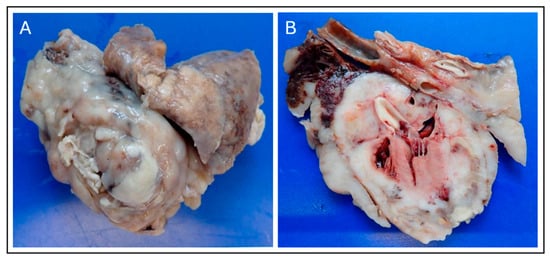

2.3. Surgical Management and Intraoperative Findings

2.4. Histopathology and Immunohistochemistry

2.6. Necropsy Findings